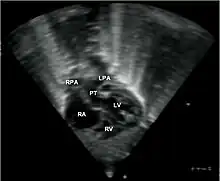

Abbreviations: RA=right atrium, RV=right ventricle, LV=left ventricle, PT=pulmonary trunk, LPA and RPA=left and right pulmonary artery.